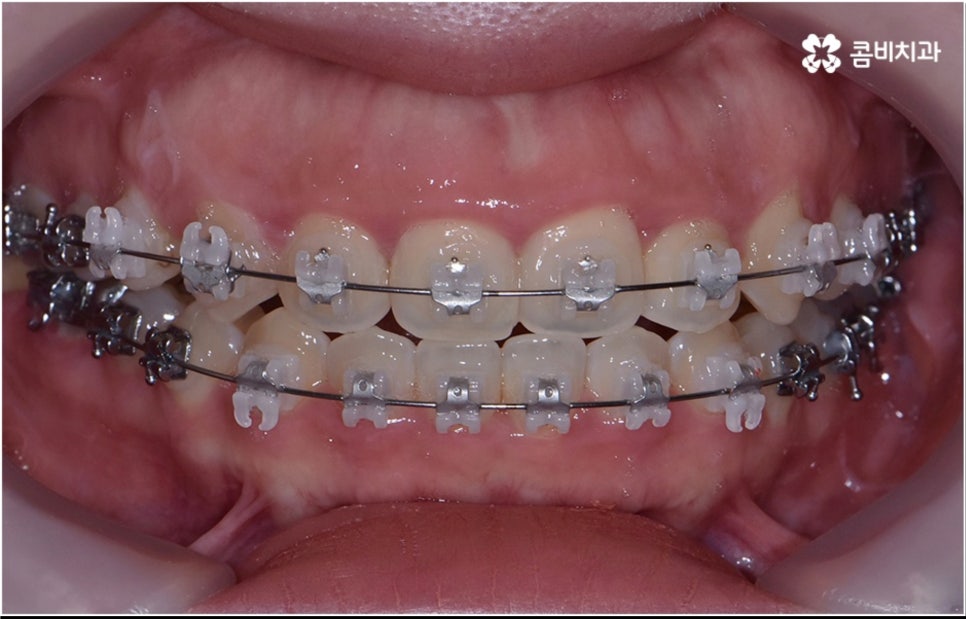

성인 치아교정 기간 이 길어지면 생활상 또는 업무상 활발한 대인 관계를 맺고 있으신 분들의 경우 교정 장치가 눈에 띄는 문제 때문에 불편함을 느끼실 수 있어요. 하지만 최근 관련 기술의 발달로 장치들 역시 심미성이 뛰어난 것들이 많이 개발되었으며 선택의 폭이 넓어졌기 때문에 치료 과정 중에도 이러한 부담감을 줄이고 보다 만족도를 높일 수 있습니다.

치아 색상의 세라믹 브라켓을 이용하는 장치들은 예전 메탈 장치 보다 심미성이 훨씬 보완되었으며, 치아 뒤쪽에 장치를 부착하여 아예 눈에 띄지 않는 설측교정장치나 언뜻 보면 티가 잘 나지 않는 얇고 투명한 특수 강화 플라스틱을 이용하는 투명교정장치를 이용하면 교정을 하고 있다고 본인이 말을 하지 않으면 잘 모를 정도로 심미성이 뛰어나기 때문에 각 장치들의 소재와 특성, 장단점에 대해서 잘 알아보고 신중한 선택을 하는 것이 중요하다고 할 수 있어요.

장치 자체는 교정 결과에 미치는 영향이 크지 않은 만큼 선택시 환자분들이 중요하게 생각하시는 부분을 반영할 수 있는 여지가 있으니 의료진과 충분한 상담을 통해 각자에게 맞는 장치를 고르시면 좋을 거예요. 또한 동일한 장치를 사용한다고 하더라도 환자분들마다 상황이 다르기 때문에 섬세한 맞춤 진료가 가능하기 위해서는 3D CT 와 같은 정밀 검진 기계가 있고 풍부한 임상 경험을 통해 뛰어난 기술력을 갖추고 있는 의료진이 처음부터 끝까지 책임 진료하는 치과에서 교정 치료를 진행하실 필요가 있으며, 이와 더불어 사후 관리까지 철저하게 이루어지는 케어 시스템이 있는지, 전공과목별 협진 시스템이 잘 운영되고 있는지 등도 꼼꼼하게 체크해 보시길 권유드리고 있어요.